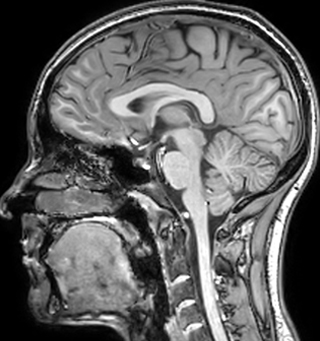

Juxtacortical MS lesion elition

Sagittal 3D FLAIR with 0.3 mm3 voxel volume acquired in 5:12 min. using Compressed SENSE showing a (juxta)cortical MS lesion.